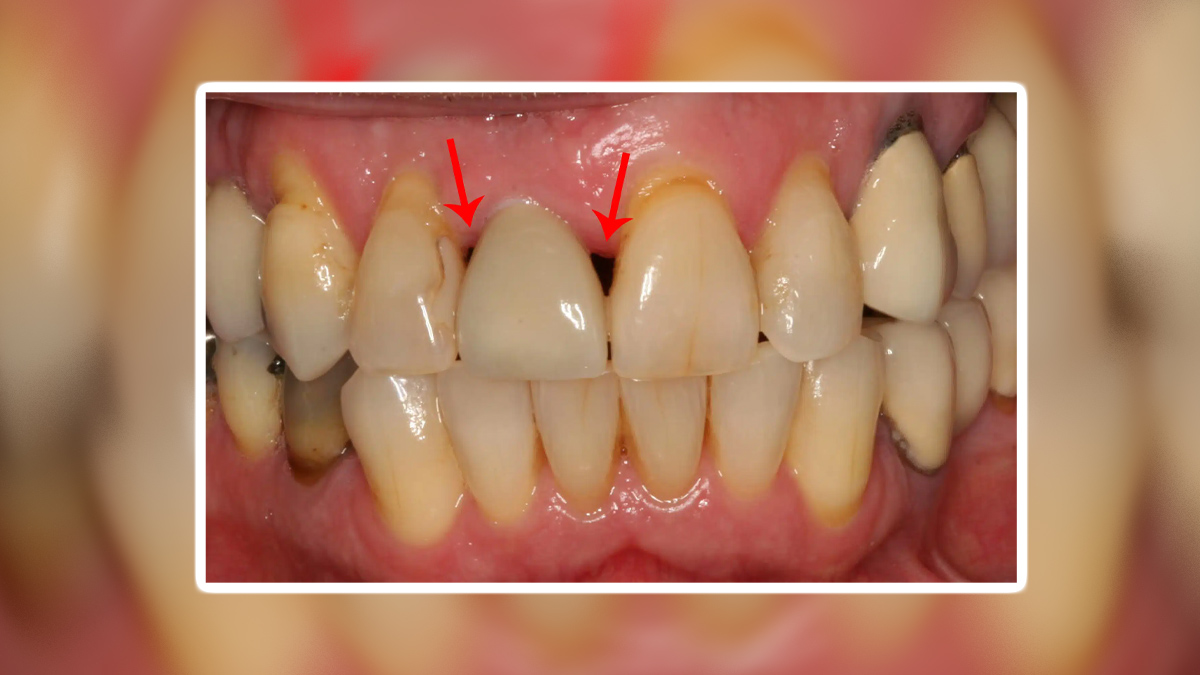

Black Triangle Between Teeth: कुछ भी खाने के लिए दांतों का स्वस्थ होना जरूरी है। अगर हम ओरल हेल्थ पर ध्यान नहीं देंगे, तो दांत जल्दी खराब हो जाएंगे। दांतों से जुड़ी समस्याओं को समझकर आप गंभीर रोगों से बच सकते हैं। ऐसी ही एक समस्या है जिसमें दांत के बीच काले दाग नजर आते हैं। दांतों के बीच में ब्लैक ट्राइएंगल (Black Triangle) एक सामान्य दंत समस्या है जिसे बहुत से लोग नजरअंदाज कर देते हैं। यह स्थिति तब होती है जब दांतों और मसूड़ों के बीच में खाली जगह बन जाती है, जो देखने में काले त्रिकोण के रूप में दिखाई देती है। इस समस्या का मुख्य कारण मसूड़ों का पीछे हटना या डैमेज के कारण होता है। इस लेख में हम ब्लैक ट्राइएंगल की कारण, लक्षण और इलाज के बारे में विस्तार से जानेंगे। इस विषय पर बेहतर जानकारी के लिए हमने लखनऊ के इन्दिरा नगर में स्थित शेखर डेंटल क्लीनिक के डॉ अनुभव श्रीवास्तव से बात की।

- सबसे स्पष्ट लक्षण है दांतों के बीच काले त्रिकोण का दिखाई देना।

- ट्राइएंगल दांतों की सुंदरता को भी प्रभावित करता है।

- दांतों के बीच इस खाली जगह के कारण खाने के कण आसानी से फंस जाते हैं।

- इससे मुंह में दुर्गंध और कैविटी की संभावना बढ़ जाती है।

- अगर यह स्थिति लंबे समय तक बनी रहती है, तो मसूड़ों में सूजन, दर्द ब्लीडिंग भी हो सकती है।